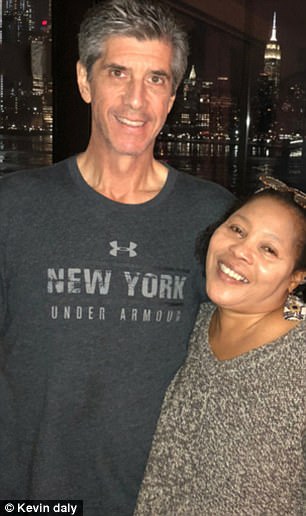

El hombre fue sometido a una tomografía computarizada en el Hospital Lenox Hill de la ciudad de Nueva York.

Los resultados fueron estremecedores, su vientre contenía “una masa extremadamente grande”, la cual se trataba de un tumor.

Sin embargo, esa masa resultó ser un raro tumor canceroso llamado liposarcoma, que crece en el tejido adiposo. Los cirujanos decidieron que el mejor tratamiento sería eliminarlo.

Al realizar las primeras incisiones, los médicos estimaron que el tumor debía pesar alrededor de unos 5,4 kilos. Pero durante la operación, pudieron notar que esa masa era más del doble del tamaño que calculaban y se había enrollado alrededor del riñón.

Los cirujanos estuvieron más de seis horas intentando eliminar el tumor, y finalmente, al removerlo por completo, puedieron ver que pesaba al rededor de 13,6 kilos.

El doctor Julio Teixeira, contó que fue el tumor más grande que extrajo en sus 30 años de práctica. Al describir cuánto pesaba esa masa, dijo: “una cosa es ver la imagen. Otra es tener este enorme tumor gigante en tus manos”.